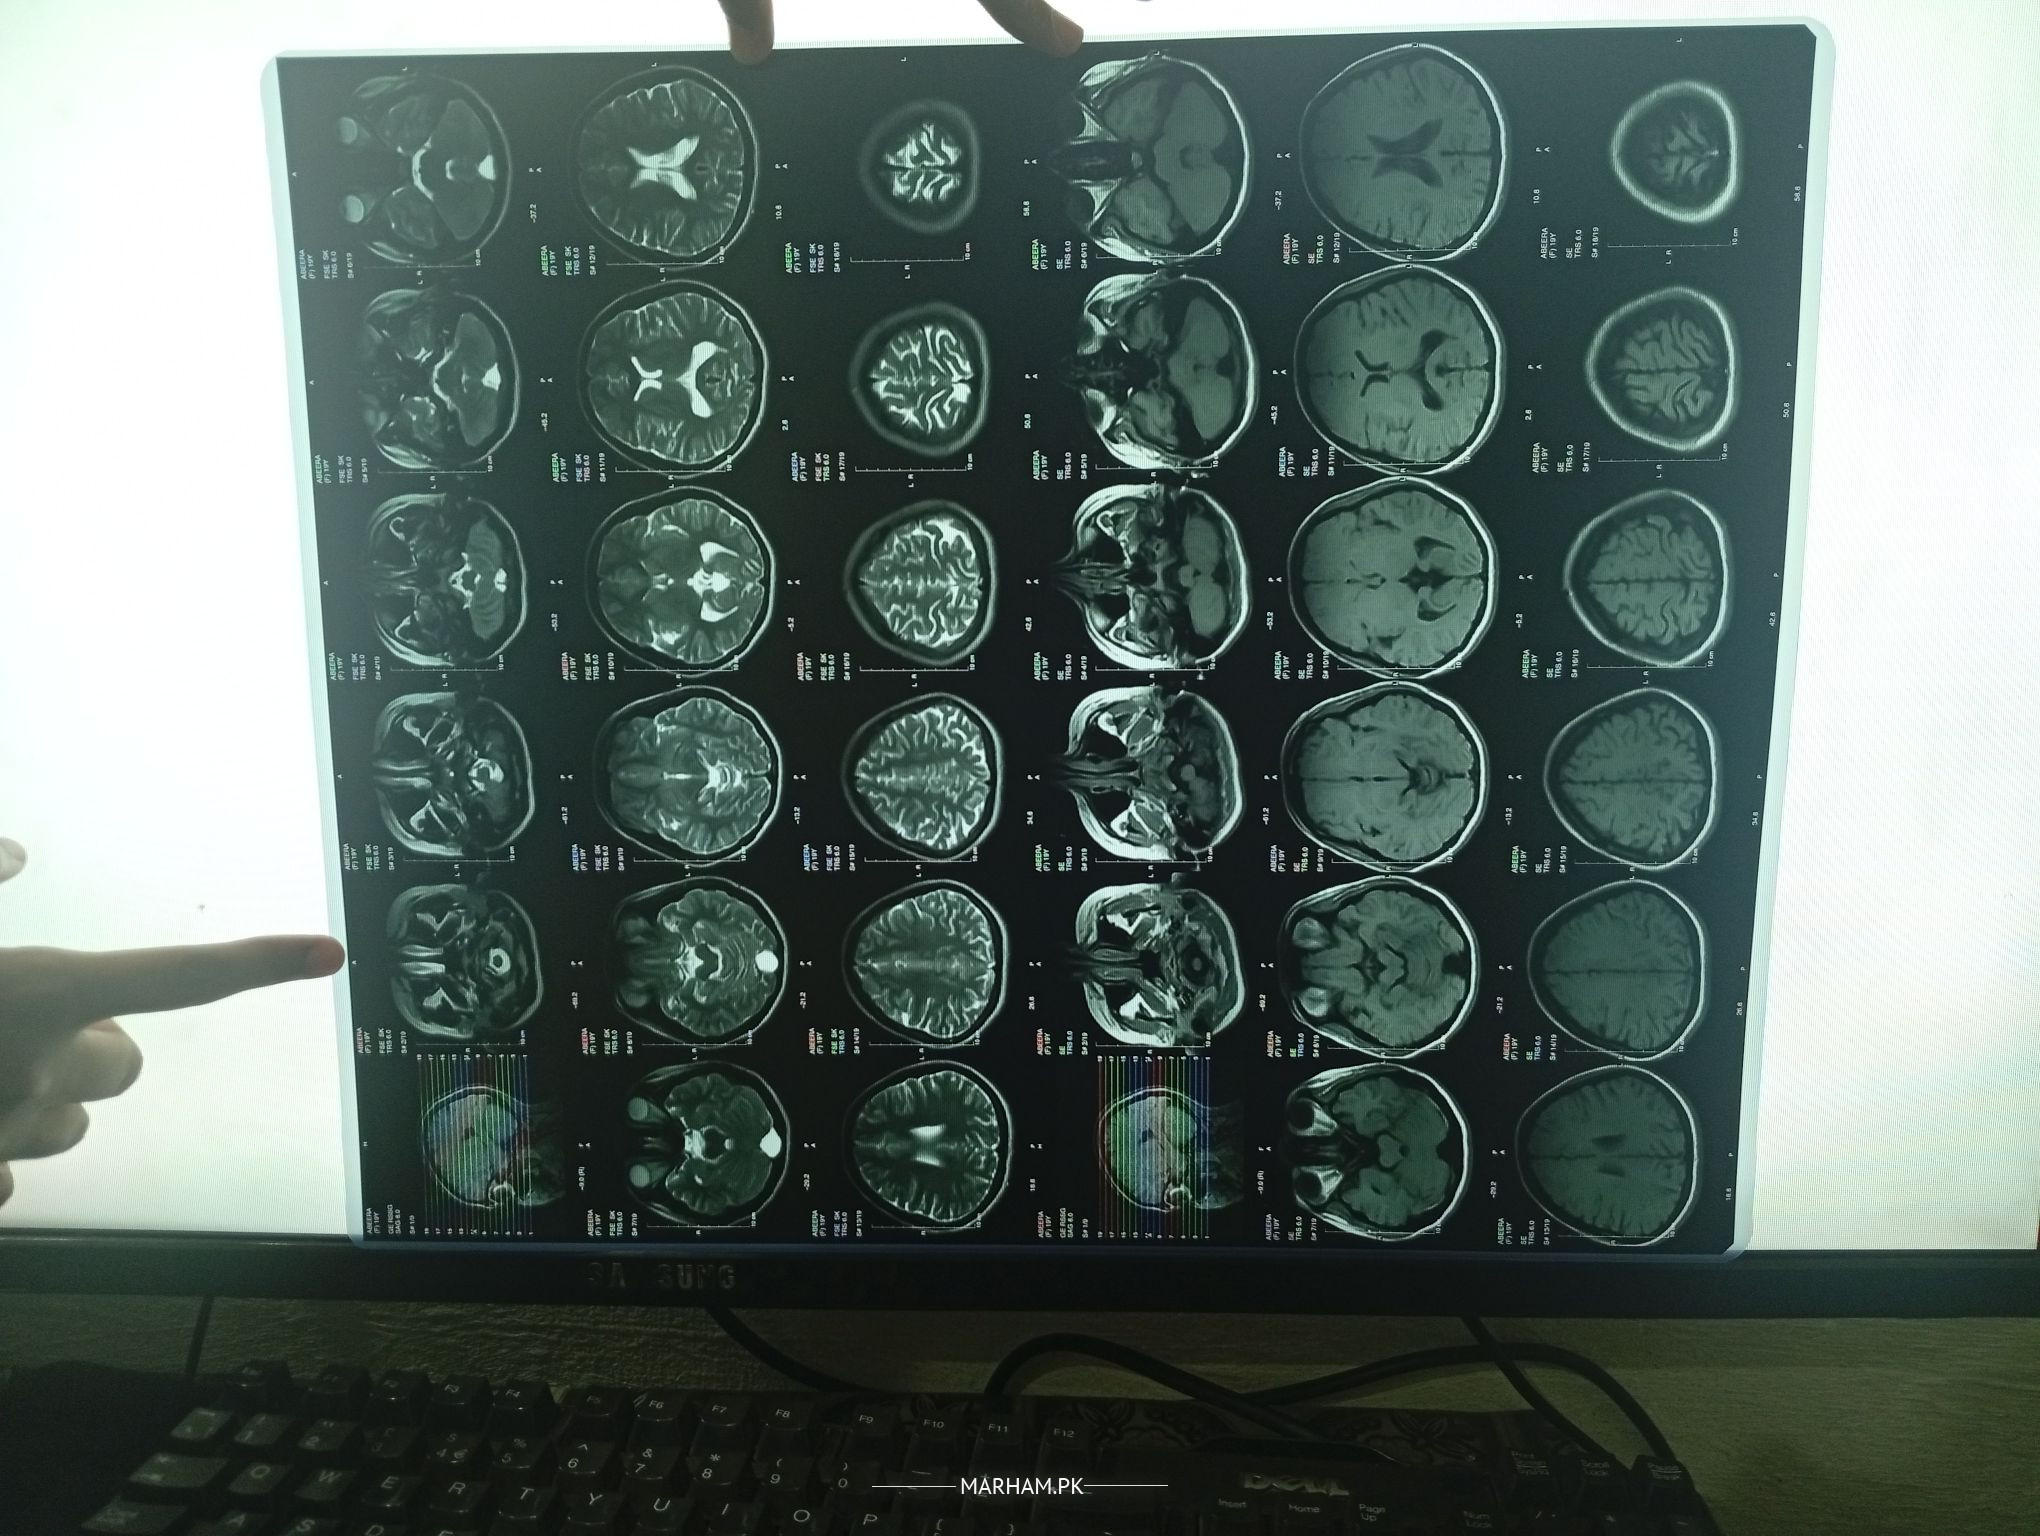

The MRI at first glance appears normal, though the report is awaited.

Need more information about the headache before can guide further.